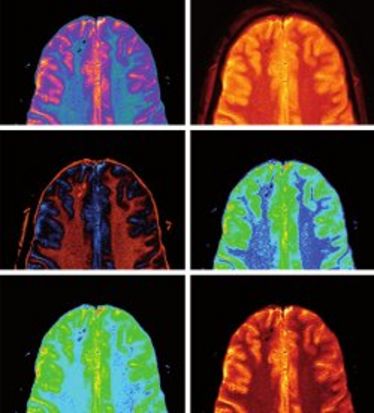

Probevortrag Ronald J. H. Borra, MD, PhD (Multimodale Bildgebung und nuklearmedizinische Therapie)

Probevortrag Ronald J. H. Borra, MD, PhD (Multimodale Bildgebung und nuklearmedizinische Therapie)

MR-Aktuell

MR-Aktuell

Lectures on MR

Lectures on MR

Cells-in-Motion brown-bag lunch: UTE phase contrast MRI for blood flow visualization in mice

Cells-in-Motion brown-bag lunch: UTE phase contrast MRI for blood flow visualization in mice